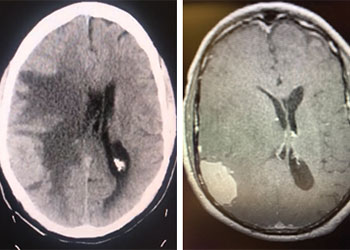

Cerebral Metastases from Non-Small Cell Lung Cancer

Author: Xavier P. J. Gaudin D.O., F.A.C.O.S., Read More!

Brain Metastasis

Author: Michael Brisman M.D., F.A.C.S., Read More!